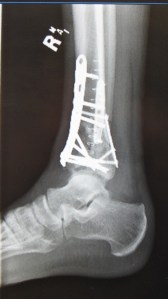

Ding-dong, the witch is dead, the ExternalFixatorNastyMedievalTortureDevice is off my leg, off my leg, off my leg. No longer am I the dog with the lampshade over his head, bumping into things everywhere I go. I’m in a cast, more mobile, and the hardware store that is my lower right leg contains three plates and twenty screws (though I count fewer on the films). Now, I must wait. Wait for the bone to re-grow, and wait for it to fill-in the areas where it went ashes to ashes, dust to dust.

It’s weird, in that my un-trained eye has seen far more gruesome-looking X-rays. But I guess the consistently grim words I hear about mine relate to the location and complexity of the fracture, not necessarily the big-looking damage. Things like the joint surface being destroyed, and that powder-back-to-bone stuff.

“I’m not going to lie,” Melinda, Dr. Desai’s excellent and normally cheerful P.A. told me at my post-op appointment Friday, her voice turning somber. “You’ve suffered a devastating injury.” She explained what they found while doing this third, and hopefully final, surgery – things like a bone “nugget” from the distal end of my tibia that had rammed several inches upward into the solid bone. They fished it

out and re-placed it. The anterior tibia had this bone plate of sorts, visible in an image I posted after the last surgery update, that had split down the middle and crumpled inward, each half partially overlapping the other. But overall the surgery went well, and they put the big pieces back together like a jigsaw puzzle, and the dust particles should eventually calcify into real bone. And, critically, they made the joint surface as smooth as possible.